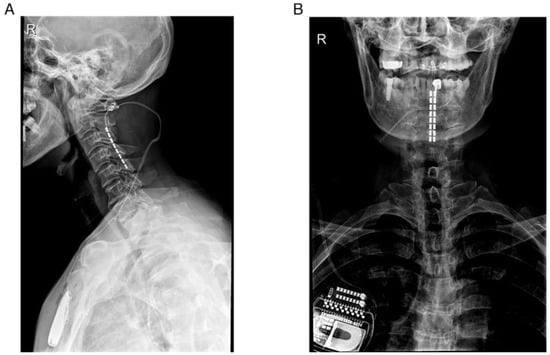

| No.1 | 53 | M | 1164.25 | PD | 13 | Yes | C2–C5 | 6 |

| No.2 | 75 | M | 550 | PD | 7 | No | C2–C5 | 6 |

| No.3 | 63 | M | 900 | PD | 4 | No | C2–C5 | 6 |

| No.4 | 60 | F | 600 | MSA-P | 6 | No | C2–C5 | 6 |

| No.5 | 61 | F | 500 | MSA-P | 6 | No | C2–C5 | 6 |

| No.6 | 58 | F | 575 | MSA-P | 4 | Yes | C2–C5 | 6 |

| No.7 | 54 | M | 300 | MSA-P | 1 | No | C2–C5 | 7 |

| No.8 | 67 | F | (-) | MSA-P | 3 | No | C2–C5 | 7 |